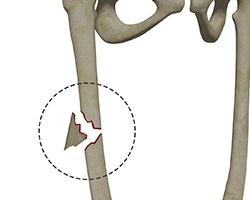

What is Femoral Shaft Fracture?

A femoral shaft fracture is a crack or break anywhere along the long and straight section of the femur (thighbone) due to high-energy trauma or low-energy trauma in osteoporotic patients. The femur is the strongest and longest bone in the body. It connects with the pelvis at the top to form the hip joint and the tibia and fibula at the bottom to form the knee joint.

Femoral fractures are classified into different types based on the site of the fracture, pattern of the fracture, and whether the muscle and skin over the bone is ruptured by the injury.

In general, femoral shaft fractures can be divided into the following common types:

- Transverse fracture: This type of fracture occurs along the femoral shaft in a horizontal line pattern.

- Oblique fracture: In this type, the fracture occurs across the shaft in an angled line pattern.

- Spiral fracture: In this type, the fracture line surrounds the shaft and occurs as a result of a twisting force.

- Comminuted fracture: This type of fracture involves a splinter or break of bone into 3 or more pieces.

- Open fracture: This is also known as a compound fracture and is the most serious form of femoral shaft fracture in which the fracture causes the bone pieces to stick out through the skin to the outer environment resulting in serious injury to surrounding soft tissue structures, such as muscles, ligaments, and tendons.